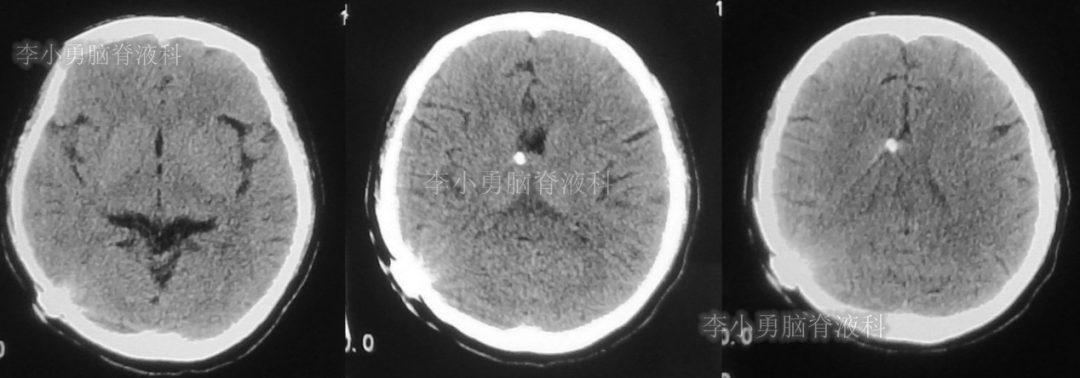

此后1个多月(2019年11月4日到2019年12月16日),患者意识一直无改善,一直呈模糊状态,多次复查头颅CT(图-12至图-20)见脑室大小反复变化不定,医生根据CT结果等反复多次调节分流泵压力(具体过程家属回忆不起)。但患者病情无好转却逐渐加重,逐渐不能咀嚼、吞咽及进食,卧床不起。

图-12:2019年11月8日头颅CT

图-13:2019年11月16日头颅CT

图-14:2019年11月19日头颅CT